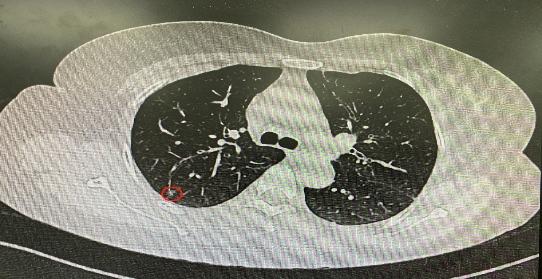

今年54歲的李女士(化名)7月初突然出現(xiàn)右上部腹痛,起初并未在意,以為稍作休息就會好轉,但疼痛卻并未消退,持續(xù)了一個星期。李女士實在難以忍受,才在家人陪伴下來到西安國際醫(yī)學中心醫(yī)院就診。胸外科二病區(qū)崔凱主任接診患者后,詳細詢問病情并查閱檢查資料,經胸部HRCT檢查,結果提示:右肺上葉后段混合密度結節(jié)影,考慮原位癌可能,即將患者收入胸腔外科二病區(qū)住院治療。

經與患者家屬溝通,崔凱主任決定行外科手術治療。為達到精準切除,術前需進行肺小結節(jié)切除前定位。由于結節(jié)位于右肺上葉后段,傳統(tǒng)經胸外穿刺術無法抵達病灶。崔凱主任與呼吸內科一病區(qū)歐陽海峰主任討論后,決定擬行LungPro全肺診療導航下染色定位。即術前通過Lung Pro導航規(guī)劃染色位置,經Lung Pro實時引導支氣管鏡抵達既定位置,注入亞甲藍染色劑標記結節(jié)位置。

使用術前規(guī)劃系統(tǒng)重建全肺3D模型,并于外科醫(yī)生討論染色位置,最終確定標記染色點—右肺上葉后段b亞段(RB2b)。術中使用P290(4.9mm外徑)標準支氣管鏡,根據導航術前規(guī)劃路徑,Lung Pro實時導航下,GS鞘管進入RB2b遠端官腔外病灶并注射亞甲藍染色劑。

一切準備就緒,7月15日,崔凱主任團隊聯(lián)合歐陽海峰主任團隊為患者行單孔胸腔鏡下右肺上葉后段切除術,手術用時128分鐘順利完成。進入胸腔后,亞甲藍染色部位明顯,患者發(fā)生癌變的右肺上葉后段被成功切除。術后標本根據染色部位迅速找到結節(jié),剖開位置兼染色位置和病灶完全符合,行術中冰凍后快速送病理檢查。經術后病理檢查,明確診斷為(右肺上葉)原位腺癌。